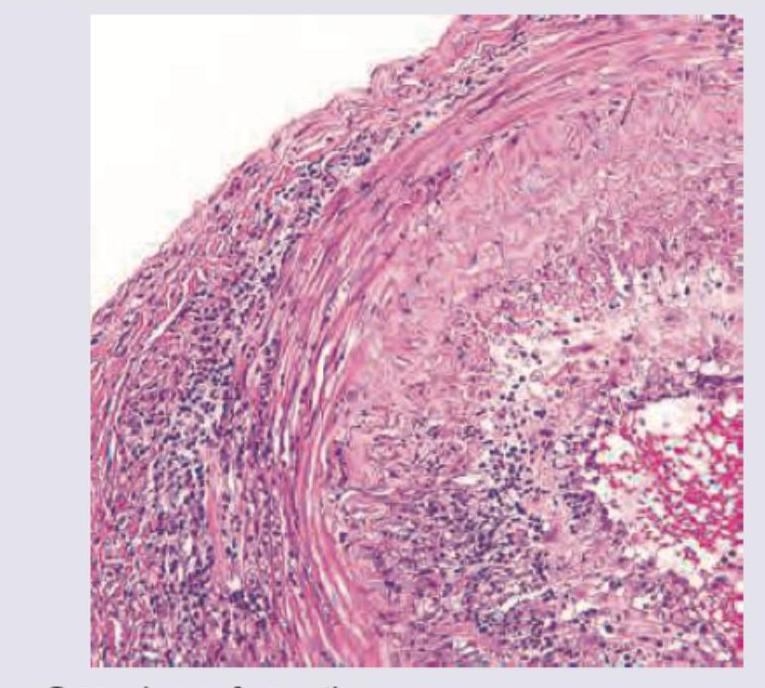

A 70-year-old retired military personnel presents with daily temporal headache and same sided blurring of vision. The Biopsy of Temporal artery was performed. All are true about the condition except:

Explanation: ***Biopsy relieves the symptoms*** - A temporal artery biopsy is a diagnostic procedure for **Giant Cell Arteritis (GCA)** [1] and does not provide symptomatic relief. - Symptomatic relief in GCA is achieved with **corticosteroid therapy**, not by the biopsy itself. *Granuloma formation* - **Giant Cell Arteritis (GCA)** is characterized by **granulomatous inflammation** of large and medium-sized arteries [1], often involving the temporal artery. - The presence of **giant cells** and **granulomas** is a hallmark histological feature of GCA [2]. *Transmural involvement* - In GCA, the inflammation typically affects all layers of the arterial wall, leading to **transmural inflammation** [2]. - This **transmural involvement** contributes to the vessel wall thickening and luminal narrowing seen in the condition [2]. *Necrotizing vasculitis* - While GCA is a form of vasculitis, it is primarily a **granulomatous vasculitis** [1] and not typically characterized by **necrotizing inflammation** of the vessel wall. - **Necrotizing vasculitis** is more commonly associated with conditions like polyarteritis nodosa or ANCA-associated vasculitides, which have different pathological features. **References:** [1] Kumar V, Abbas AK, et al.. Robbins and Cotran Pathologic Basis of Disease. 9th ed. Diseases of Infancy and Childhood, pp. 515-516. [2] Kumar V, Abbas AK, et al.. Robbins and Cotran Pathologic Basis of Disease. 9th ed. Diseases of Infancy and Childhood, pp. 516-517.